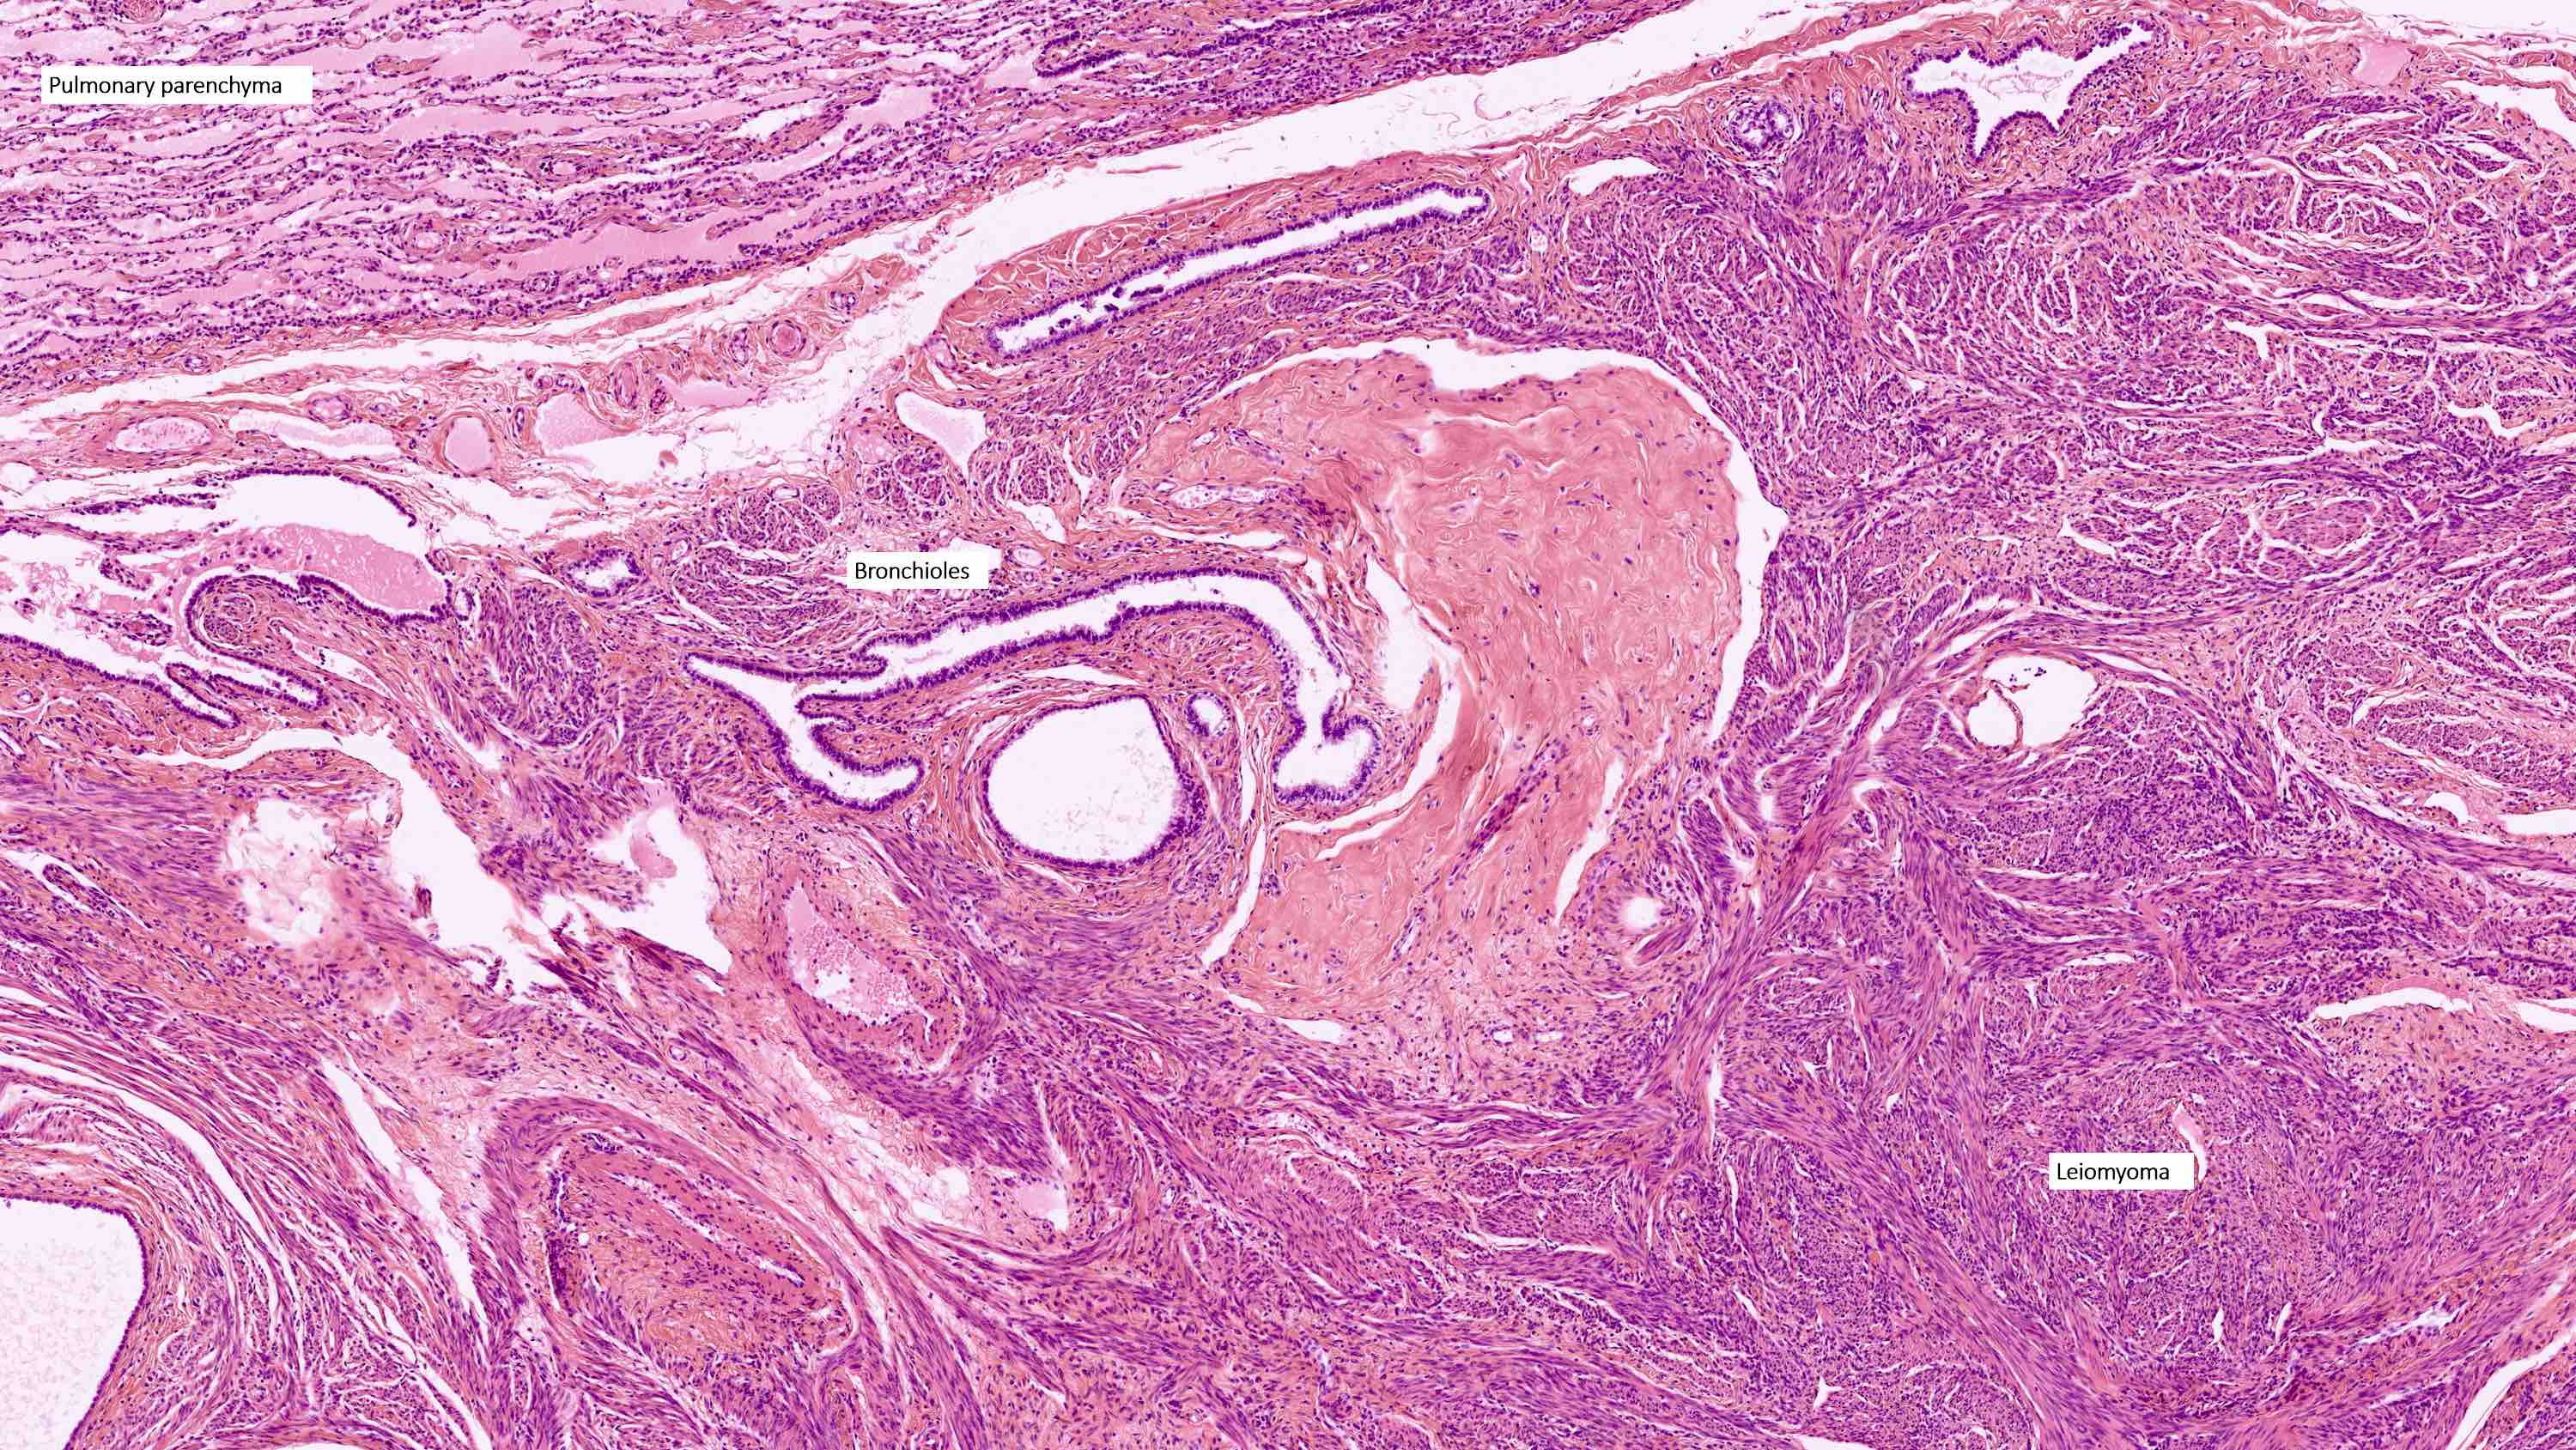

- Rare, benign appearing smooth muscle tumor in lung; may represent hematogenous spread of a uterine leiomyoma or a metastasis of a well differentiated leiomyosarcoma of low malignant potential (Mod Pathol 2006;19:130)

- Usually women 36 - 64 years, mean 44 years, with history of uterine leiomyoma

- Lung is most common site, sparing bronchus and pleura; also reported in lymph nodes, retroperitoneum, skin, bone, spine, skull base, heart

- Usually multiple nodules, up to a few centimeters in size

Microscopic (histologic) description

- Conventional / usual leiomyoma (spindle):

- Well defined borders

- Normocellular

- Intersecting fascicles of monotonous spindle cells with indistinct borders, eosinophilic cytoplasm, cigar shaped nuclei (with tapered ends) and small nucleoli

- Atypia: absent or mild

- Mitoses: rare (in general < 5/10 high power fields)

- Blood vessels with thick walls

- With or without infarct type necrosis, hyalinization, calcification, cystic change

Microscopic (histologic) images

Contributed by Sabrina Croce, M.D., Ph.D., Kristina Doytcheva, M.D., Jennifer A. Bennett, M.D. (Case #508) and @Andrew_Fltv on Twitter